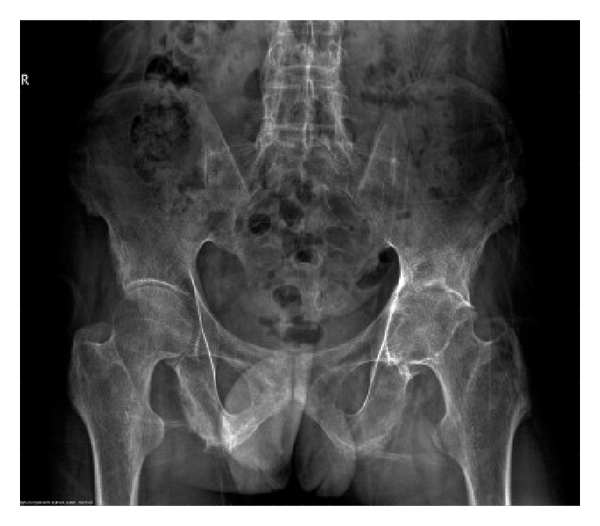

Preoperative characteristics of patients are listed in Table 1. The mean age and disease duration of patients were 37.1 ± 9.0 years (range: 24–52 years) and 13.7 ± 12.4 years (range: 2–40 years), respectively. HLA-B27 was positive in all patients. RF and ANA were negative. No patient had a history of iritis. Five patients had elevated ESR (5/7, 71.4%). Six patients had increased CRP (6/7, 85.7%). Radiographic evaluation of hips showed narrowed joint spaces ranging from 0 to 7 mm, including 3 of 7 patients with complete disappearance of the joint space (Figure 1). Serum levels of IgG and IgG4 were not measured.

(a)

(b)

(c)

(d)